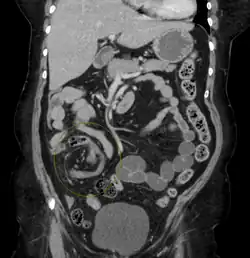

Coronal view of sigmoid volvulus with "whirlpool sign" -

CT scan of a small bowel volvulus. It shows two juxtaposed segments of narrowing, which is the spot of mesentery rotation. The other signs indicate strangulation. -